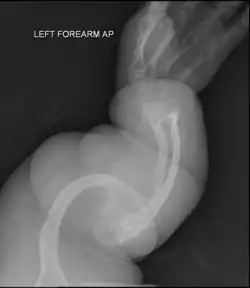

- Type V – Having the same clinical features as type IV, it can be clinically distinguished by observing a "mesh-like" appearance to a bone biopsy under a microscope. Type V can be further distinguished from other types of OI by the "V triad": an opaque band (visible on X-ray) adjacent to the growth plates; hypertrophic calluses (abnormally large masses of bony repair tissue) which form at fracture sites during the healing process; and calcification of the interosseous membrane of the forearm,[50] which may make it difficult to turn the wrist.[1]: 429 Other features of this condition may include pulled elbow, and, as in other types of OI, long bone bowing and hearing loss.[64] Cases of this type are caused by mutations in the IFITM5 gene on chromosome 11p15.5.[64][49] The separation of type V from type IV OI, its clinical type, was initially suggested even before its genetic cause was known, by Glorieux et al. in 2000.[50][65] Type V is relatively common compared to other genetically defined types of OI—4% of OI patients at the genetics department of the Brazilian Hospital de Clínicas de Porto Alegre were found to have it.[66]

Diagnosis is typically based on medical imaging, including plain X-rays, and symptoms. In severe OI, signs on medical imaging include abnormalities in all extremities and the spine.[97] As X-rays are often insensitive to the comparatively smaller bone density loss associated with type I OI, DEXA scans may be needed.[5]: 1514